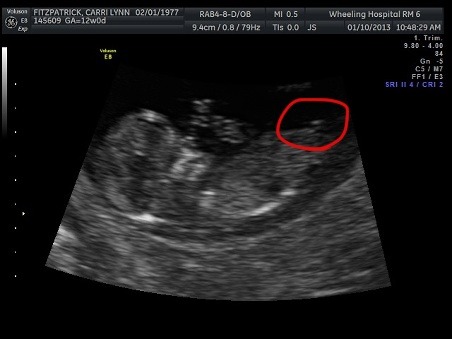

I am not sure if this is a nub or not the same as my other pictures. The baby was moving and the tech pointed out leg was moving when snapped the picture. I circled what I believed to be the nub and posted the pic without the circle as well.